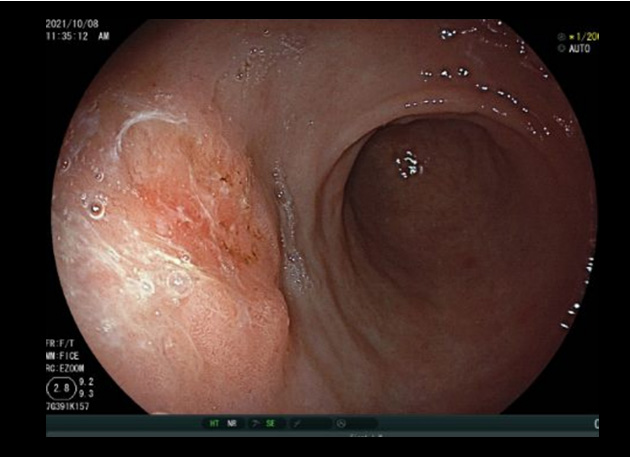

남자와 폐경 후 여성분들에게 나타나는 빈혈은 위장관의 악성질환에서 조금씩 피가 나는 것이 원인일수 있기 때문에, 반드시 위, 대장내시경을 시행하여 위암이나 대장암이 있는지 확인이 필요합니다. 만성질환에 동반된 빈혈은 환자분이 적응하면서 어지러운 증상을 호소하지 않기 때문에, 불편감을 못 느낄수도 있으나 그냥 지나치지 말고 반드시 내시경검사를 통하여 확인할 필요가 있다는 것을 다시 한번 깨달은 증례였습니다.